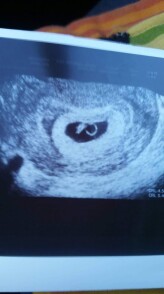

Dobry den. 21.1.2019 jsem byla na gynekologii na potvrzeni tehotenstvi. Podle posledni MS jsem mela byt 7+1, ale podle UZ mi doktor rekl, ze plod je mnohem mensi. Srdicko bylo videt, CLR meril 2x, nejdrive nameril 4,5mm a pak 5,4mm. Ani se nezminil na kolikaty tyden to tedy vypada. Jen rekl, ze jestli se nic nestane a nezmeni, ze mam prijit 15.2.2019. Je to normalni? Trochu me tim vydesil. V priloze prikladam foto z UZ.Dekuji za odpoved.

Dobrý den, podle obrázku vypadá těhotenství na cca probíhající sedmý týden, což by odpovídalo i přítomnosti srdeční akce. Stáří těhotenství dle poslední menstruace nemusí být vždy přesné, určitě je třeba se orientovat dle UZ. Kontrola za 14 dní se mi zdá naprosto v pořádku.